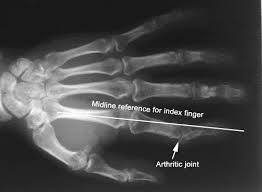

Diagnosis and Testing for Arthritis in the Fingers

If you experience symptoms such as knuckle pain in one finger or persistent stiffness, it’s important to see a rheumatoid arthritis doctor for proper evaluation.

Diagnostic tests may include:

- X-rays to detect joint damage or bone spurs